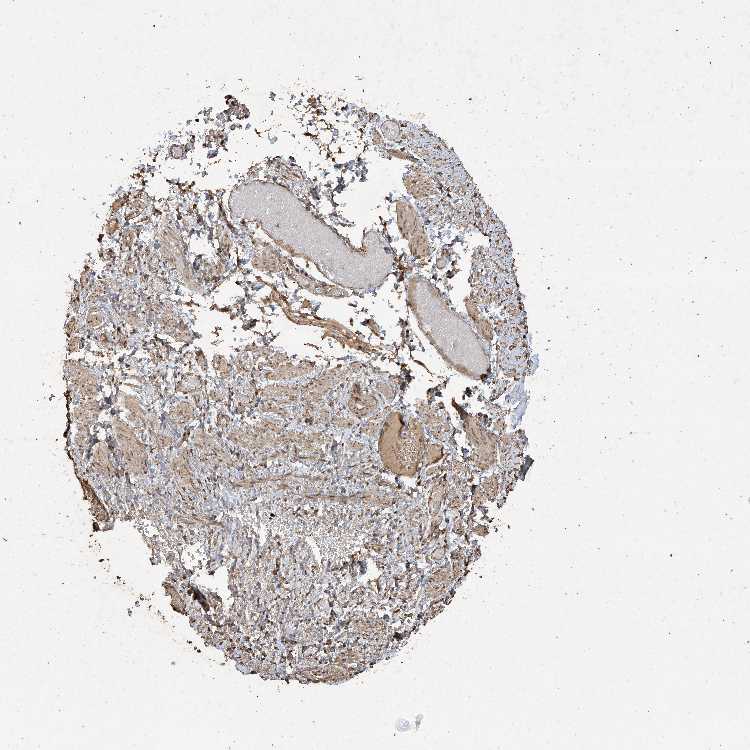

SULT2B1